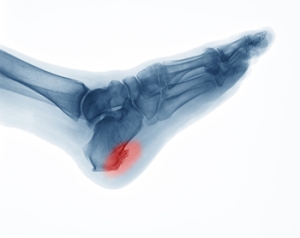

Heel spurs, or “enthesophytes,” develop on the heel of the foot. There are two types of heel spurs associated with different heel problems. One type of heel spur is called a Plantar Spur. It is linked to a problem called “Heel Spur Syndrome” and is a bone spur that develops on the bottom of the heel, on the sole of the foot where the plantar fascia (a band of fibrous tissue that stretches along the bottom of the foot) connects to the heel bone. People who have plantar fasciitis are prone to developing these kinds of spurs, which are the bone’s response to stress from straining foot muscles and ligaments, overstretching the plantar fascia, or repeated tearing of the thin lining of the heel bone. They are also associated with age, obesity, and osteoarthritis. Heel spurs are less likely to feel painful. The other type of heel spur is a Dorsal Spur and is connected to a problem called “Insertional Achilles Tendonitis,” a condition where a bone spur develops at the back of the heel, where the Achilles tendon fits into the bone. If you notice a bony protrusion on the heel of your foot or have pain in this area, it is best to consult with a podiatrist who can diagnose the problem and recommend proper treatment.

Heel spurs are formed by calcium deposits on the back of the foot where the heel is. This can also be caused by small fragments of bone breaking off one section of the foot, attaching onto the back of the foot. Heel spurs can also be bone growth on the back of the foot and may grow in the direction of the arch of the foot.

Heel spurs are the result of calcium deposits that cause bony protrusions on the underside of the heel. Heel spurs are usually painless, but they have the potential to cause heel pain. Heel spurs tend to be associated with plantar fasciitis, which is a condition that causes inflammation of the band of connective tissue that runs along the bottom of the foot. They most often occur to athletes whose sports involve a lot of running and jumping.

It is possible to have a heel spur without showing signs of any symptoms. However, if inflammation develops at the point of the spur’s formation, you may have pain while walking or running. In terms of diagnosis, sometimes all a doctor needs to know is that the patient is experiencing a sharp pain localized to the heel to diagnose a heel spur. Other times, an x-ray may be needed to confirm the presence of a heel spur.